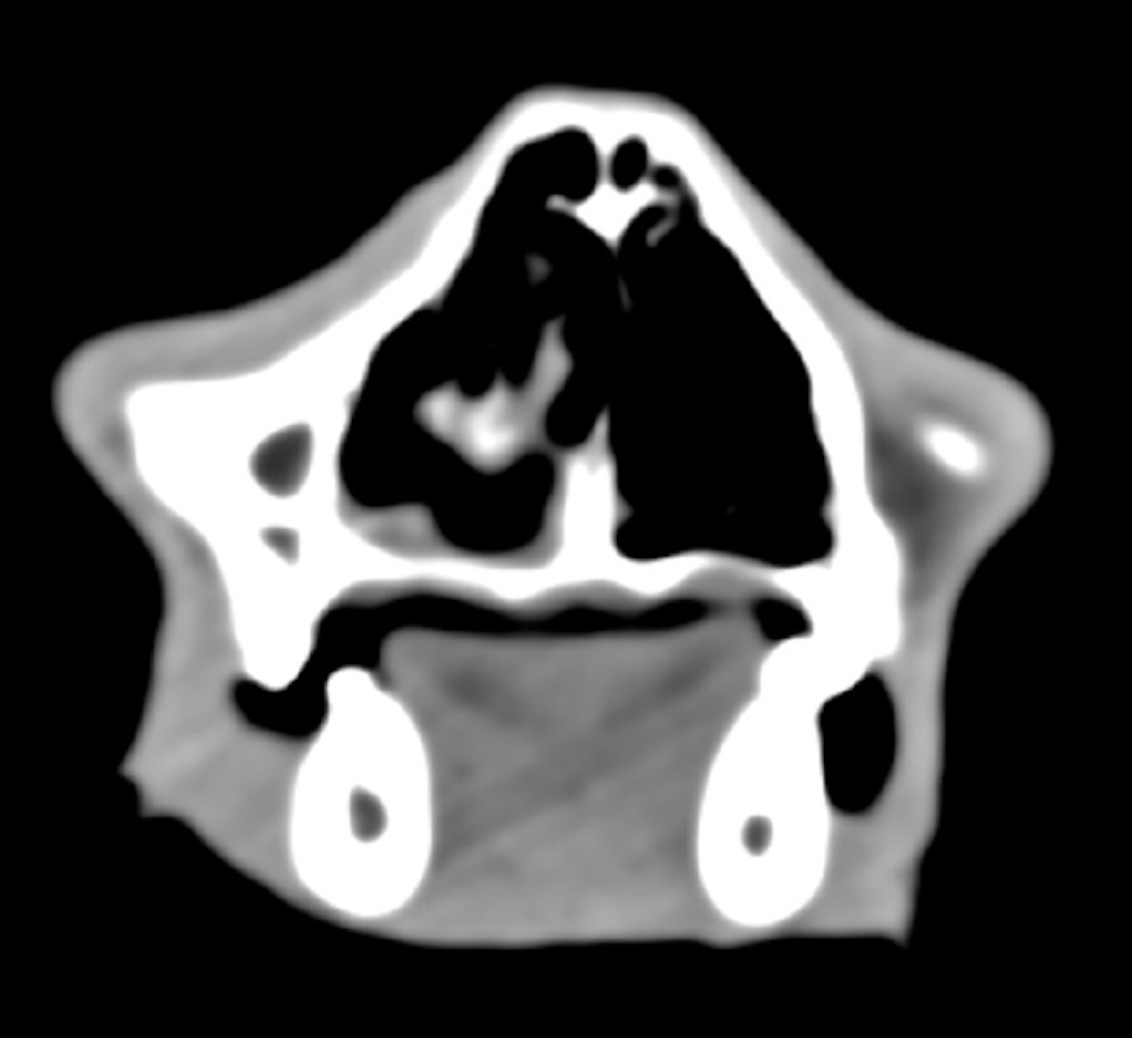

Zur Abklärung der Symptomatik ist zunächst eine Computertomographie mit anschließender Endoskopie geplant. In der Computertomographie zeigt sich der rechte Sinus nasalis im rostralen und mittleren Anteil nahezu vollständig weichteildicht verschattet, nur vereinzelt finden sich rostral Lufteinschlüsse. Der kaudale Bereich ist belüftet, die Lamina cribrosa unverändert. Septum und Conchenstruktur im Bereich der Verschattung sind partiell erhalten. Die Weichteilverschattung nimmt zentral Kontrastmittel auf, setzt sich rostral an den Rändern abgegrenzt in die linke Nasenhöhle fort und wölbt sich von dorsal in den Nasopharynx. Die Lymphknoten zeigen sich unauffällig.

Im vorliegenden Fall ist aufgrund der eindeutigen Befundlage die Strahlentherapie angezeigt, sodass der Patient acht Tage nach der Rhinoskopie und dem Staging (CT Thorax und Abdomenultraschall) zur Planung der Strahlentherapie und Computertomographie vorgestellt wurde. Für die CT wurde, wie bei Nasenhöhlentumoren üblich, eine Vakuummatratze sowie ein Beißkeil angefertigt. Die Strahlentherapie wurde in 10 Fraktionen, werktäglich über zwei Wochen mit einer Gesamtdosis von 42 Gy im Bereich des Primärtumors und mit einer Gesamtdosis von 32 Gy im Bereich der mandibularen und retrophangealen Lymphknoten durchgeführt. Der Patient hat sowohl die Strahlentherapie als auch die Narkosen gut vertragen und wurde bei ungestörtem Allgemeinbefinden entlassen.

Zum aktuellen Zeitpunkt 12 Monate nach Strahlentherapie ist der Kater klinisch in einem guten Allgemeinzustand, die Kontrollen zeigen ein weitgehend normales Bild. Die Besitzer berichten lediglich von gelegentlichem Niesen und intermittierender, geringgradiger Rhinorrhoe. Die Computertomographie 7 Monate nach Strahlentherapie zeigt den Tumor in kompletter Remission und keine relevanten Veränderungen der Nasenhöhlen. Zusammenfassend hat sich der Patient von einem Zustand mit deutlich eingeschränkter Fitness und reduziertem Allgemeinzustand hin zu einem klinisch weitestgehend unauffälligen Kater entwickelt. Zum aktuellen Zeitpunkt spricht nichts für eine absehbare Veränderung und so genießen Besitzer und Patient die aktuelle Situation in vollen Zügen.